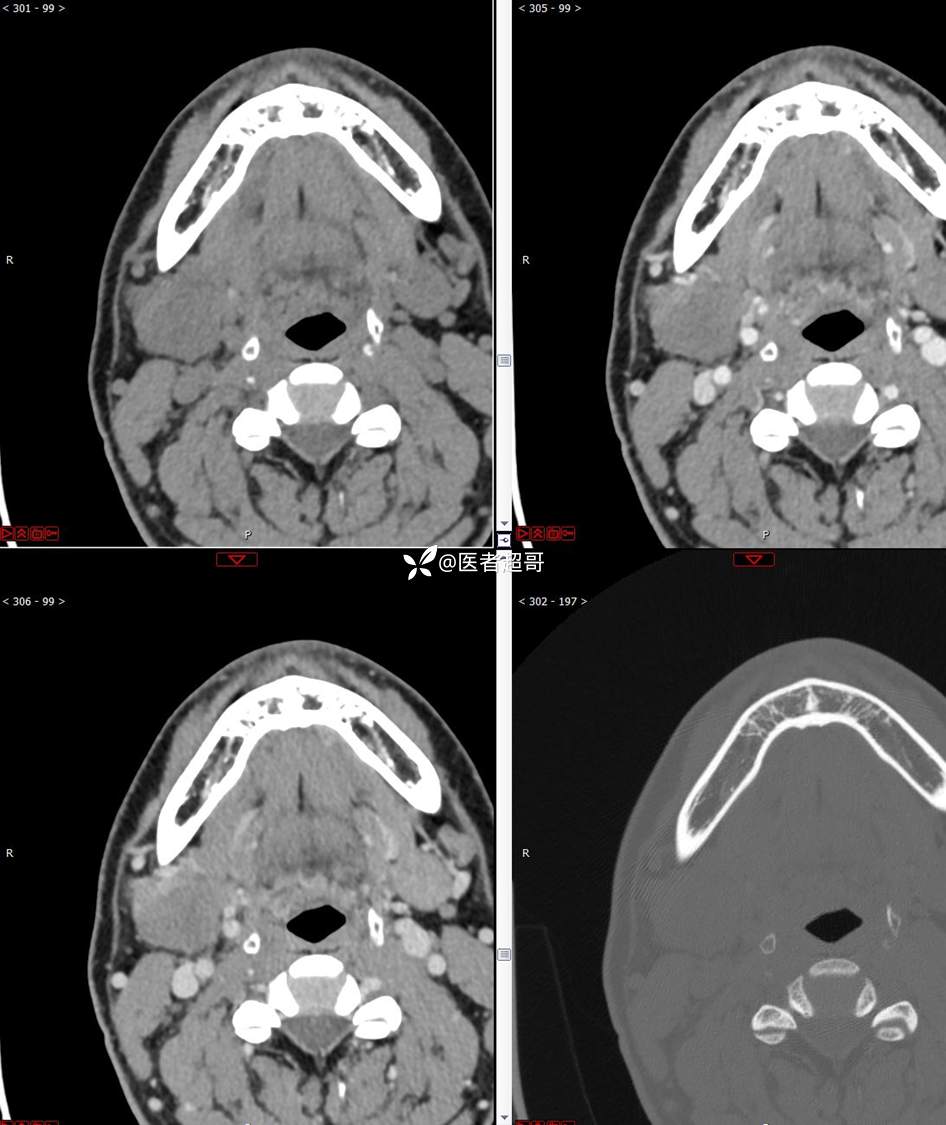

颌下腺结节:青年男性,颌下区无痛性肿物,请分析~~~

主 诉:发现右颌下区无痛性肿物1年。

现病史:患者于1年前发现右颌下区一肿物,肿物约“葡萄粒”大小,无疼痛不适,无进食时颌下区肿胀及疼痛不适。2023-10-1就诊于市中医院行超声检查;未予治疗。肿物体积无明显变化,求进一步治疗就诊于我院门诊,门诊以“颌下肿物”收入我科。患者自发病以来,神志清,精神佳,食欲好,睡眠好,大小便正常,近期体重无明显变化。